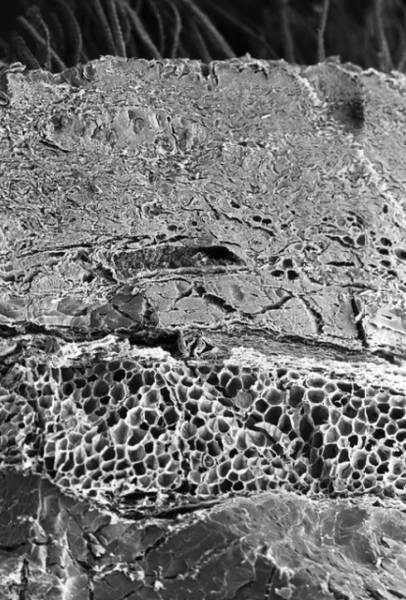

Кожа